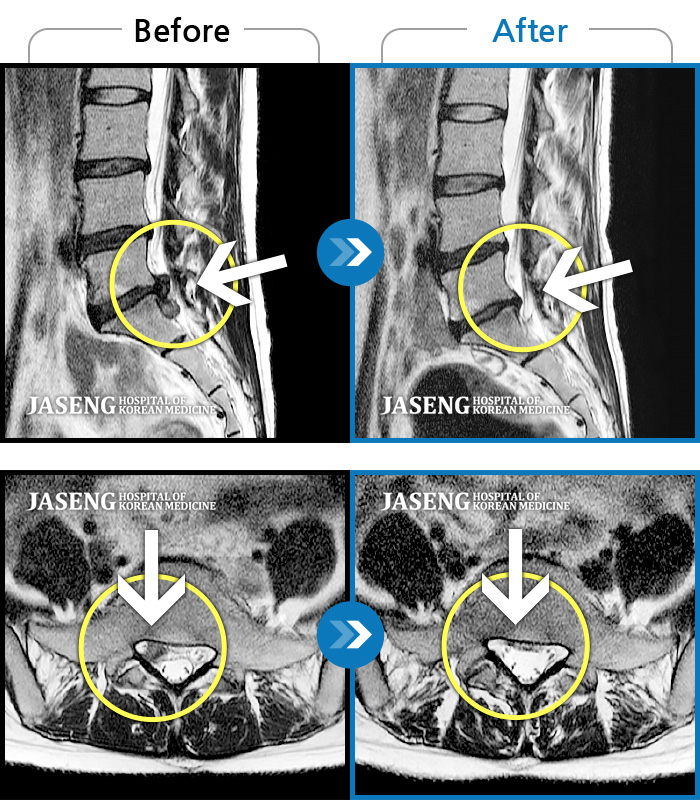

Before

After

통증 및 우측 엉치 우측 종아리 땡기는 통증이 심하여 일상생활이 안되는 상태로 내원하셨던 분입니다.

2023.11.21 ~ 2024.06.05